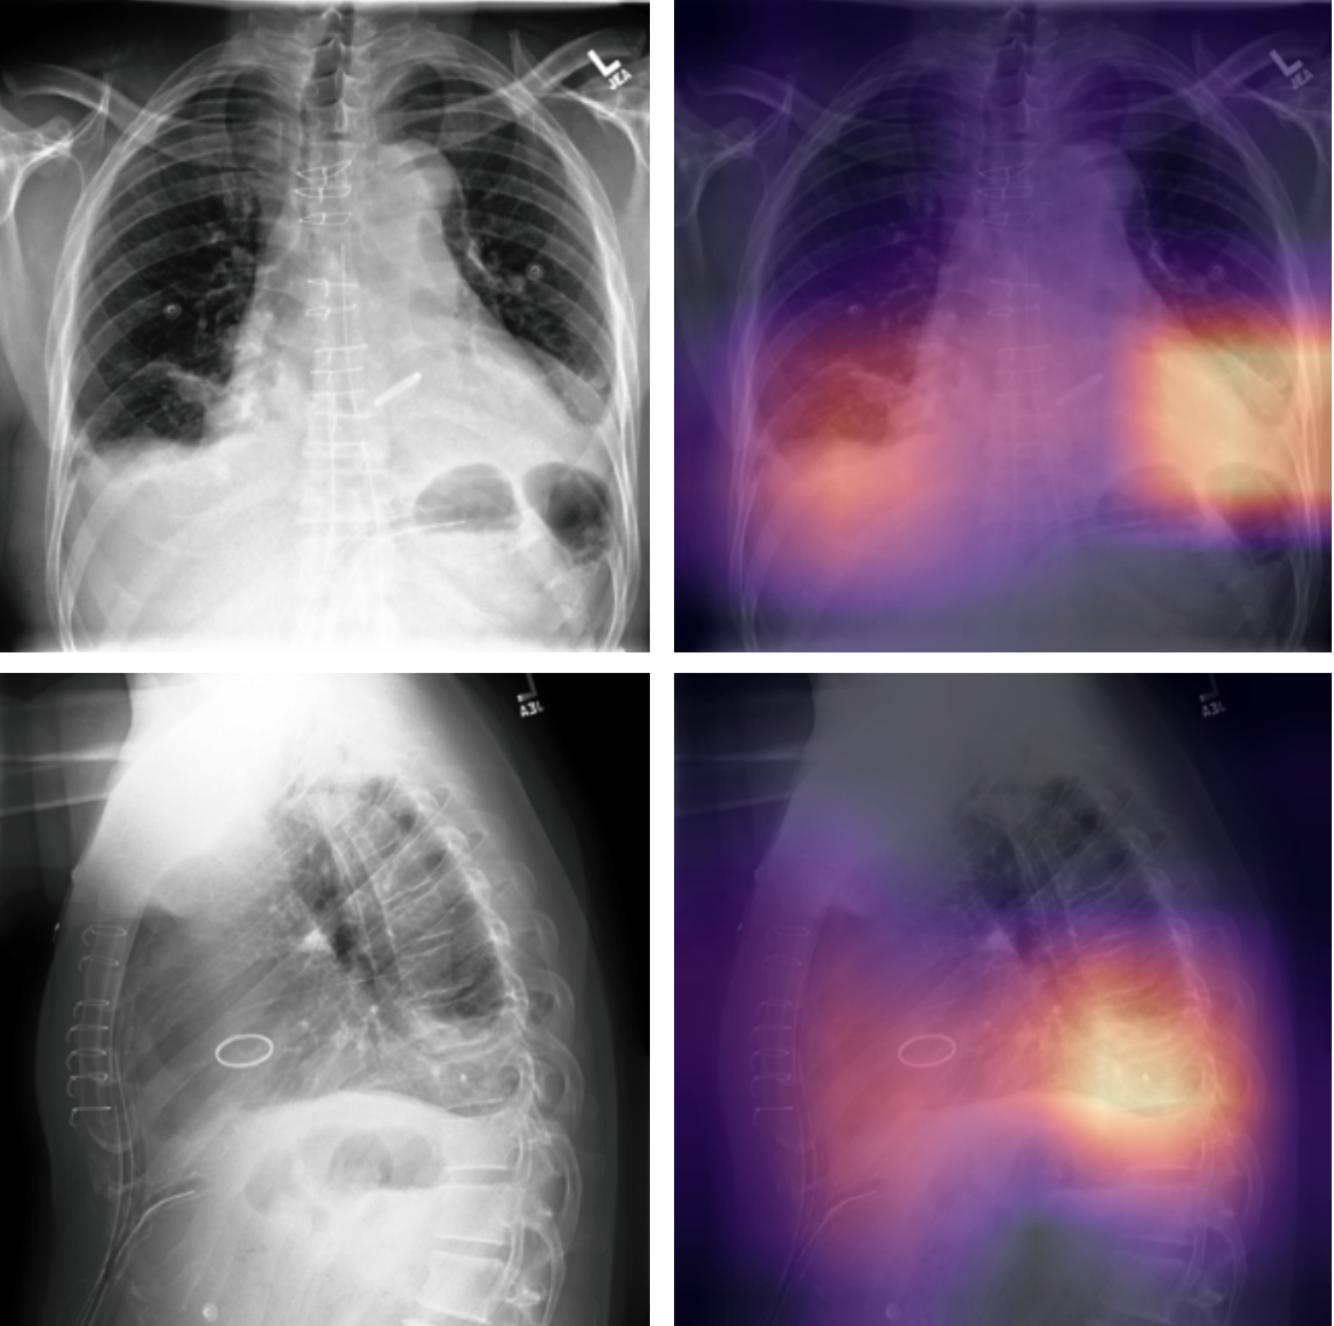

| Stanford (CheXpert) |

Clinical narratives (radiology reports) + images (X-rays) | Rule-based NLP pipeline (dictionary matching, negation detection) to label 14 conditions per report; produced labels for >220k X-ray images; used labels to train CNN diagnostic models |